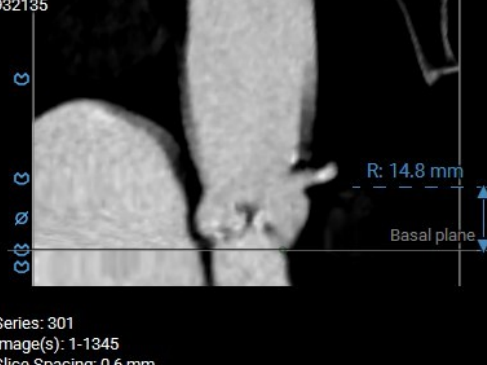

术前CT分析

主动脉根部测量

Annulus 20.7mm

LVOT 21.3mm

钙化积分 612

SOV

27.9*26.8*27.1mm

STJ 22.6mm

AAO 28.8mm

-

三叶瓣

流出道直筒型

重度钙化

STJ及升主无明显扩张

瓣上结构测量

瓣上2mm

20.5mm

瓣上4mm

19.9mm

瓣上6mm

20.7mm

瓣上8mm

20.2mm

瓣上10mm

20.8mm

瓣上12mm

21.9mm

冠脉风险评估

LCA Height

RCA Height

左冠开口高度较低,结合瓦氏窦大小,预估冠脉风险相对较低。

左室测量

左室内径可,心室壁增厚,心尖较薄,注意导丝位置及形态,避免左室损伤。